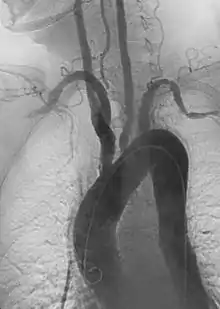

- Aortic aneurysms include thoracic, abdominal and thoracoabdominal aneurysms. Treatment strategies are customized depending on the location, size, rate of growth and extent of the aneurysm as well as the medical comorbidities of the patient. For example, an intact, small but slowly growing aneurysm may be safely monitored with serial imaging for months or years before elective repair is considered. Elective endovascular aortic grafting is now routinely attempted when possible. Endovascular aortic repair (EVAR) refers to treatment of an abdominal aortic aneurysm, while thoracic endovascular aortic repair (TEVAR) is performed on the thoracic aorta. A ruptured aneurysm may be taken emergently for open, endovascular or combination repair.

A variety of endovascular grafts are available, and each has advantages and disadvantages depending on the characteristics of the aneurysm and patient.[89]